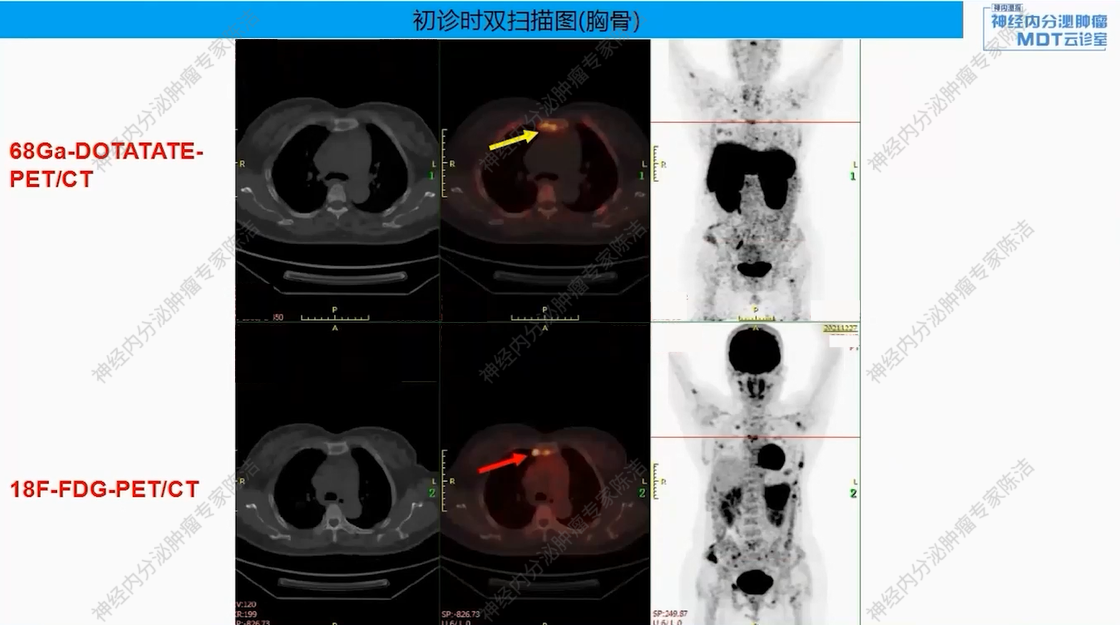

18F-FDG-PET-CT提示:胰尾部见巨大肿物(约8.6*7.2*7.8 cm),FDG代谢明显增高。胰体部另见一小结节(约0.8*0.7 cm),FDG代谢轻度增高。全身多发骨质改变,FDG代谢增高。

68Ga-DOTANOC-PET-CT提示:胰尾部巨大肿块,DOTANOC摄取阴性;胰体部小结节,DOTANOC摄取阳性。甲状旁腺区多发结节,DOTANOC摄取阳性;垂体区稍增大,DOTANOC摄取阳性。

核医学科徐俊彦教授:本病例双扫描PET显像体现了该患者多发肿瘤间异质性。胰尾大病灶(胰岛素瘤)呈SSTR阴性、FDG阳性,这符合约50%胰岛素瘤不表达SSTR的特征。而胰体小病灶呈SSTR阳性、FDG轻度增高。垂体区在SSTR(有生理性摄取)和FDG(无生理性摄取)上均呈阳性,提示垂体瘤可能。骨骼病灶呈SSTR和FDG“双阳性”,高度提示为SSTR阳性的NET转移,但建议对于骨病灶,可对相对表浅的病灶行骨穿以进一步明确骨病灶情况。从最初影像可见髂骨存在明显骨质破坏,甚至骨皮质整体受损,因此骨转移的可能性较大。然而,鉴于该患者同时患有甲状旁腺瘤,甲状旁腺瘤常伴发棕色瘤改变,故目前不能排除甲状旁腺继发的骨改变的可能。

该患者以低血糖为首发症状,影像学发现胰腺占位、甲状旁腺及垂体病变,并检测到MEN1胚系基因大片段缺失而最终确诊。胰腺上同时存在SSTR阴性的胰岛素瘤和SSTR阳性的神经内分泌肿瘤,且骨转移灶(SSTR阳性)极可能来源于后者(胰体小病灶),而非引起主要症状的前者(胰尾大病灶)。